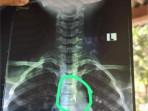

Jagat maya dihebohkan dengan beredarnya foto hasil rontgen diduga milik seorang bocah SD di Kabupaten Bojonegoro Jawa Timur.